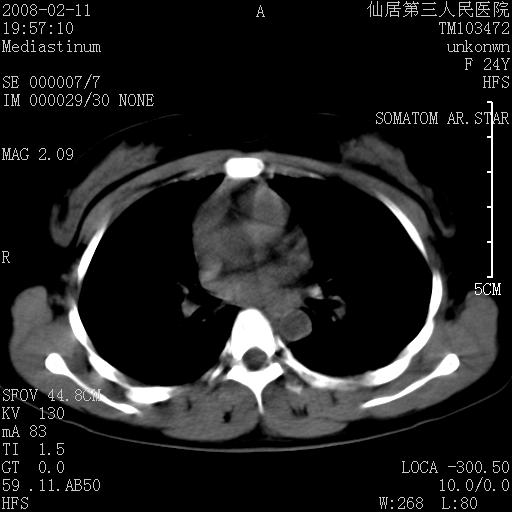

以下是引用zjzjr在2008-2-12 14:32:00的发言:[br]胸腺大点,是不是胸腺瘤或胸腺增生